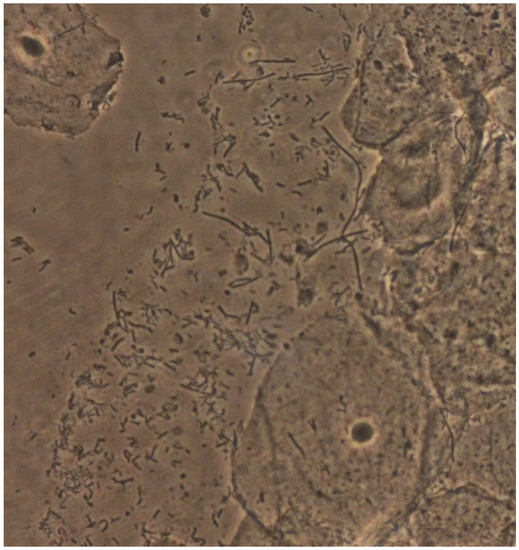

Vaginal Leptothrix: An Innocent Bystander?

- Vieira-Baptista, P.; Grincevičienė, Š.; Oliveira, C.; Fonseca-Moutinho, J.; Cherey, F.; Stockdale, C.K. The International Society for the Study of Vulvovaginal Disease Vaginal Wet Mount Microscopy Guidelines: How to Perform, Applications, and Interpretation. J. Low. Genit. Tract Dis. 2021, 25, 172–180. [Google Scholar] [CrossRef]